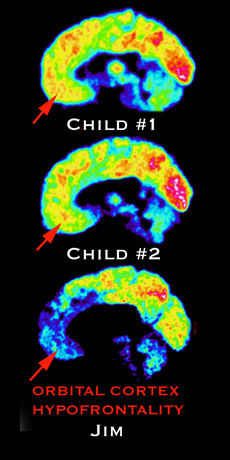

Two healthy brains and Jim's which seems to have a gap in ethics centres.

Like the killers he studied, part of his orbital cortex, the area of the brain which controls ethics and morality, was inactive. He also had several genes associated with aggression and violence.